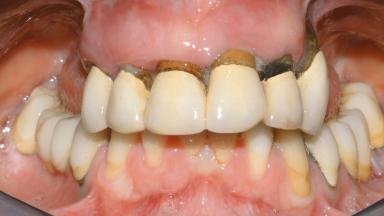

Conventional Loading of Eight Implants in the Maxilla and Final Restoration with a Full-Arch Gold-Ceramic FDP

A 35-year-old Caucasian female presenting with advanced periodontal disease involving both the maxillary and the mandibular dentition was referred for evaluation. The patient, a non-smoker in good general health, requested treatment for recurrent periodontal abscesses, tooth mobility, and discomfort during chewing, as well as restoration of her missing teeth with a fixed prosthesis to improve mastication and esthetics. All residual maxillary teeth exhibited plaque deposits, deep pockets, bleeding on probing, and class III mobility and were evaluated as hopeless. All residual mandibular teeth except tooth 37 could be maintained after periodontal therapy.

Prosthesis Type FDP

Defining Characteristics Fully edentulous upper jaw to be rehabilitated with an implant-borne fixed dental prosthesis

Loading Protocol Conventional or early